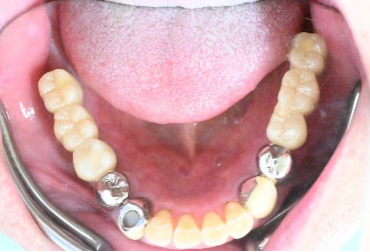

Before

▼初診時に使用していた部分入れ歯を装着したところ

▼インプラント埋入前

After

▼インプラント埋入後